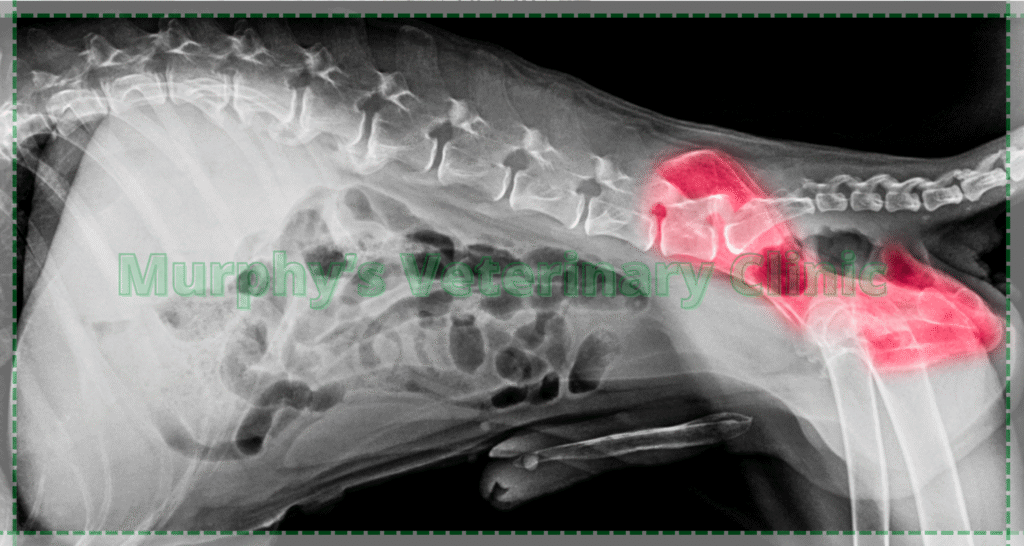

Role of Pet Imaging in Diagnosing Skeletal and Movement Disorders

Pet imaging is highly valuable in detecting skeletal and musculoskeletal conditions. For example, X-rays can quickly identify bone fractures, dislocations, or deformities. In more complex situations, CT scans provide detailed 3D imaging of the affected area. Consequently, this helps veterinarians plan appropriate surgical interventions, physical therapy routines, or immobilization strategies to ensure proper recovery.

Fracture Detection

Clearly shows the location and severity of broken bones.

Joint and Arthritis Analysis

Identifies changes in joint spacing and surrounding bone structures.

Dislocation and Misalignment

Helps spot bone or joint displacement without exploratory surgery.